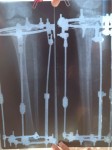

Дата операции 04.02.2014г.

Дата снятия аппаратов 05.05.2014г.

Срок лечения 89 дней.

Николь, ножки твои просто супер! Смотрела на них и восхищалась результатом! Поздравляю с окончанием аппаратного периода!